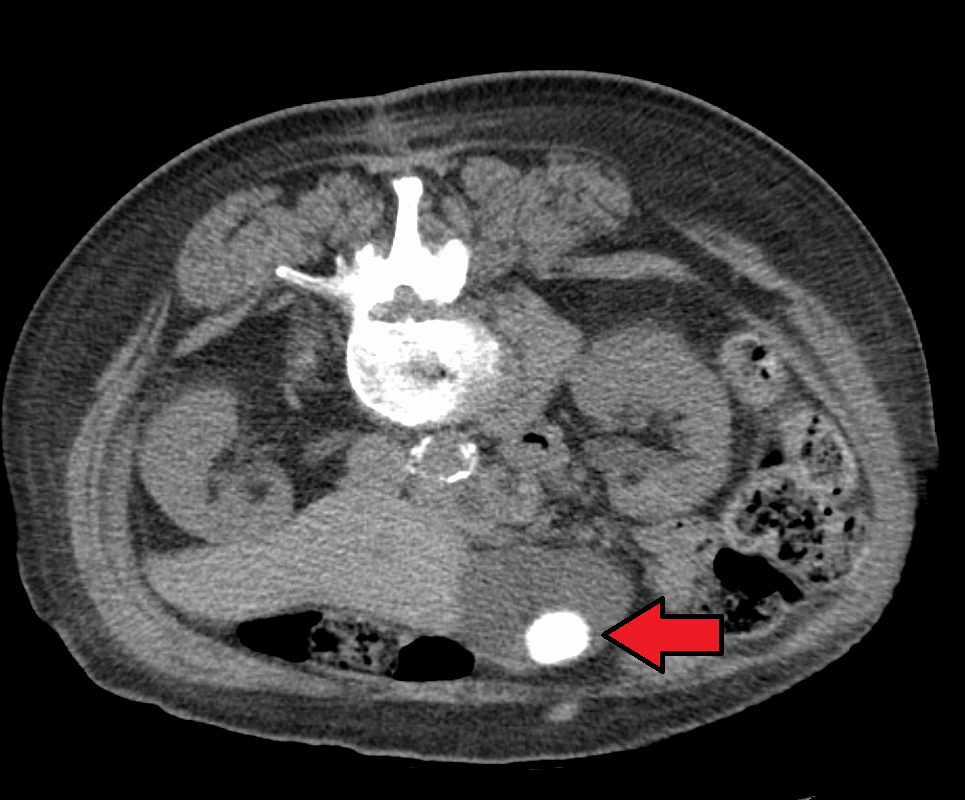

CT에서 보이는 큰 담석